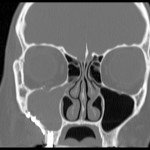

Aspetti biologici e clinici delle sinusiti odontogene

Sinusiti e rinosinusiti costituiscono le complicanze potenziali di alcune condizioni patologiche o trattamenti di competenza odontoiatrica. Interessante come sia stato recentemente appurato il coinvolgimento eziopatogenico di specie batteriche in grado di svilupparsi all'interno del biofilm.